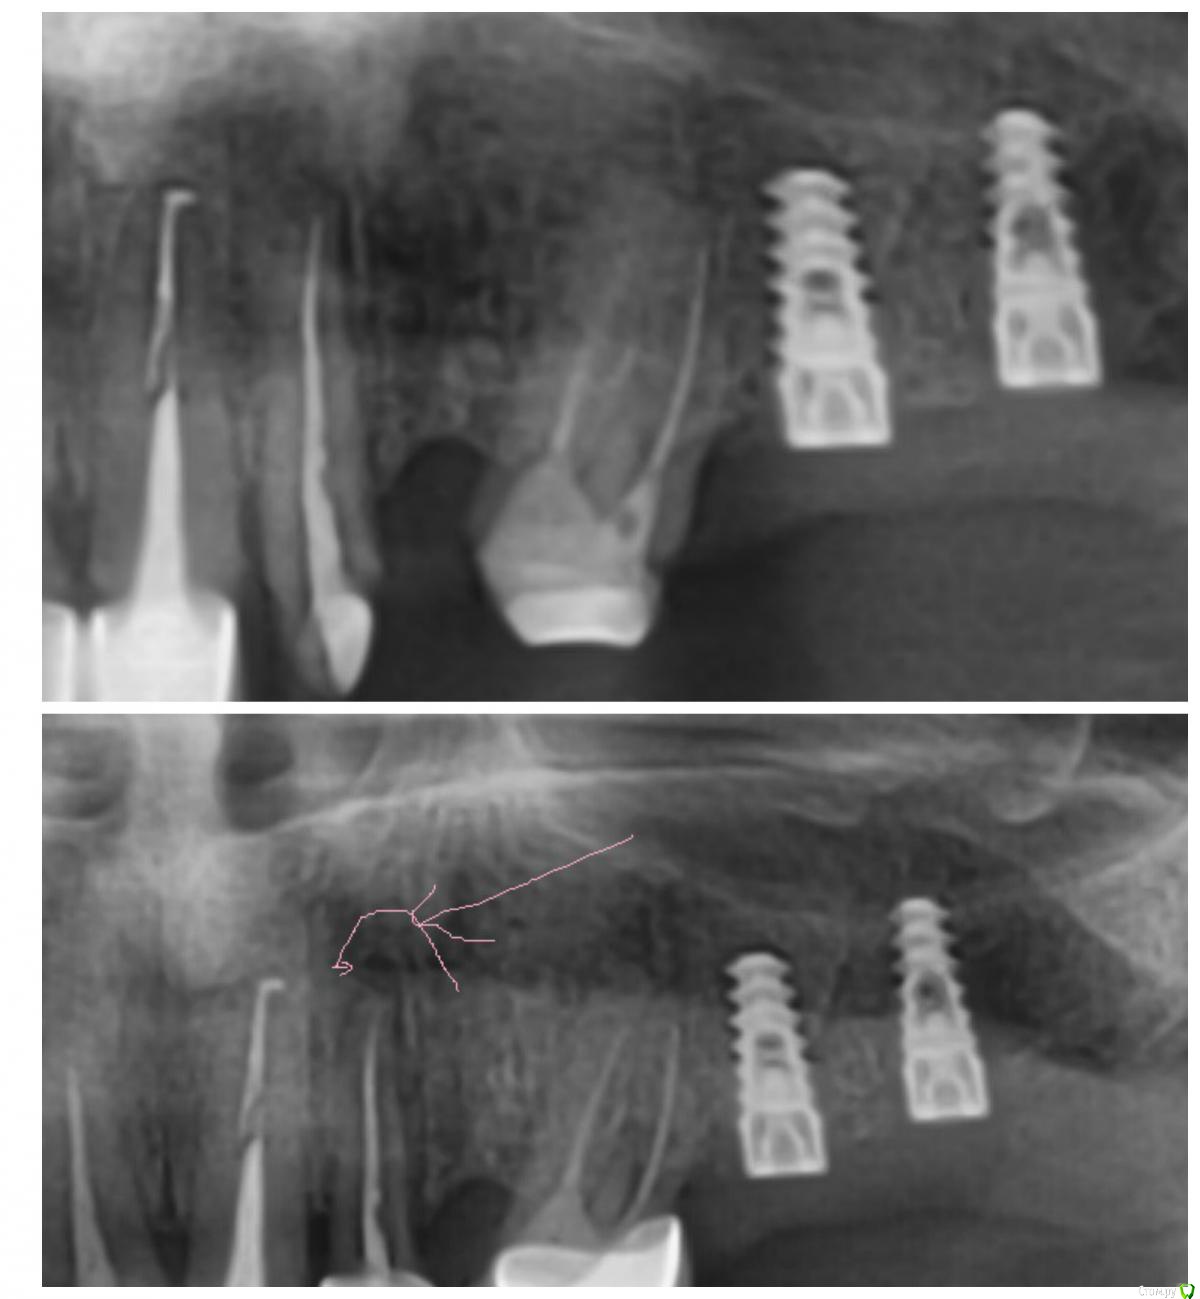

ileanacosanzeana Опубликовано 31 января, 2017 Поделиться Опубликовано 31 января, 2017 Три недели назад поставили мост, рисунок 1, все было нормально, потом я сделалa через три недели рентген ( поставили 3 импланта снизу) и увидела черное пятно над зубом (рисунок снизу) .Что это и что делать? не поставили имплант потому что имплантолог сказал что мало места... Ссылка на комментарий

chervoncevdaniil Опубликовано 31 января, 2017 Поделиться Опубликовано 31 января, 2017 Там хроническое воспаление из-за не совсем качественной пломбировки каналов,рано или поздно заболит Ссылка на комментарий

chervoncevdaniil Опубликовано 31 января, 2017 Поделиться Опубликовано 31 января, 2017 И внезапного нет,на первом снимке воспаление тоже видно Ссылка на комментарий

Доктор Добрых Дел Опубликовано 31 января, 2017 Поделиться Опубликовано 31 января, 2017 Альтернатива снятию моста только резекция верхушки корня с ретроградной пломбировкой канала. Но в идеале перед резекцией все равно нужно качественно перепломбировать канал. Ссылка на комментарий

___49___ Опубликовано 1 февраля, 2017 Поделиться Опубликовано 1 февраля, 2017 (изменено) 1 - собрать анамнез и определить динамику ( по русски - когда лечили , по какому диагнозу, это уже было при лечении или появилось после ).2- если динамика отрицательная и гранулема растет (что судя по снимку скорее всего так) произвести резекцию с пломбированием канала с другой стороны (ретроградно), или пройти канал заново обычным способом .3 - если динамика положительная (в чем сомневаюсь) - наблюдать чтобы не стала отрицательной (то о чем вам сказал ваш доктор). P\S при отрицательной динамике инфекция может развиваться вовлекая все новые и новые близлежащие ткани. Изменено 1 февраля, 2017 пользователем ___49___ Ссылка на комментарий